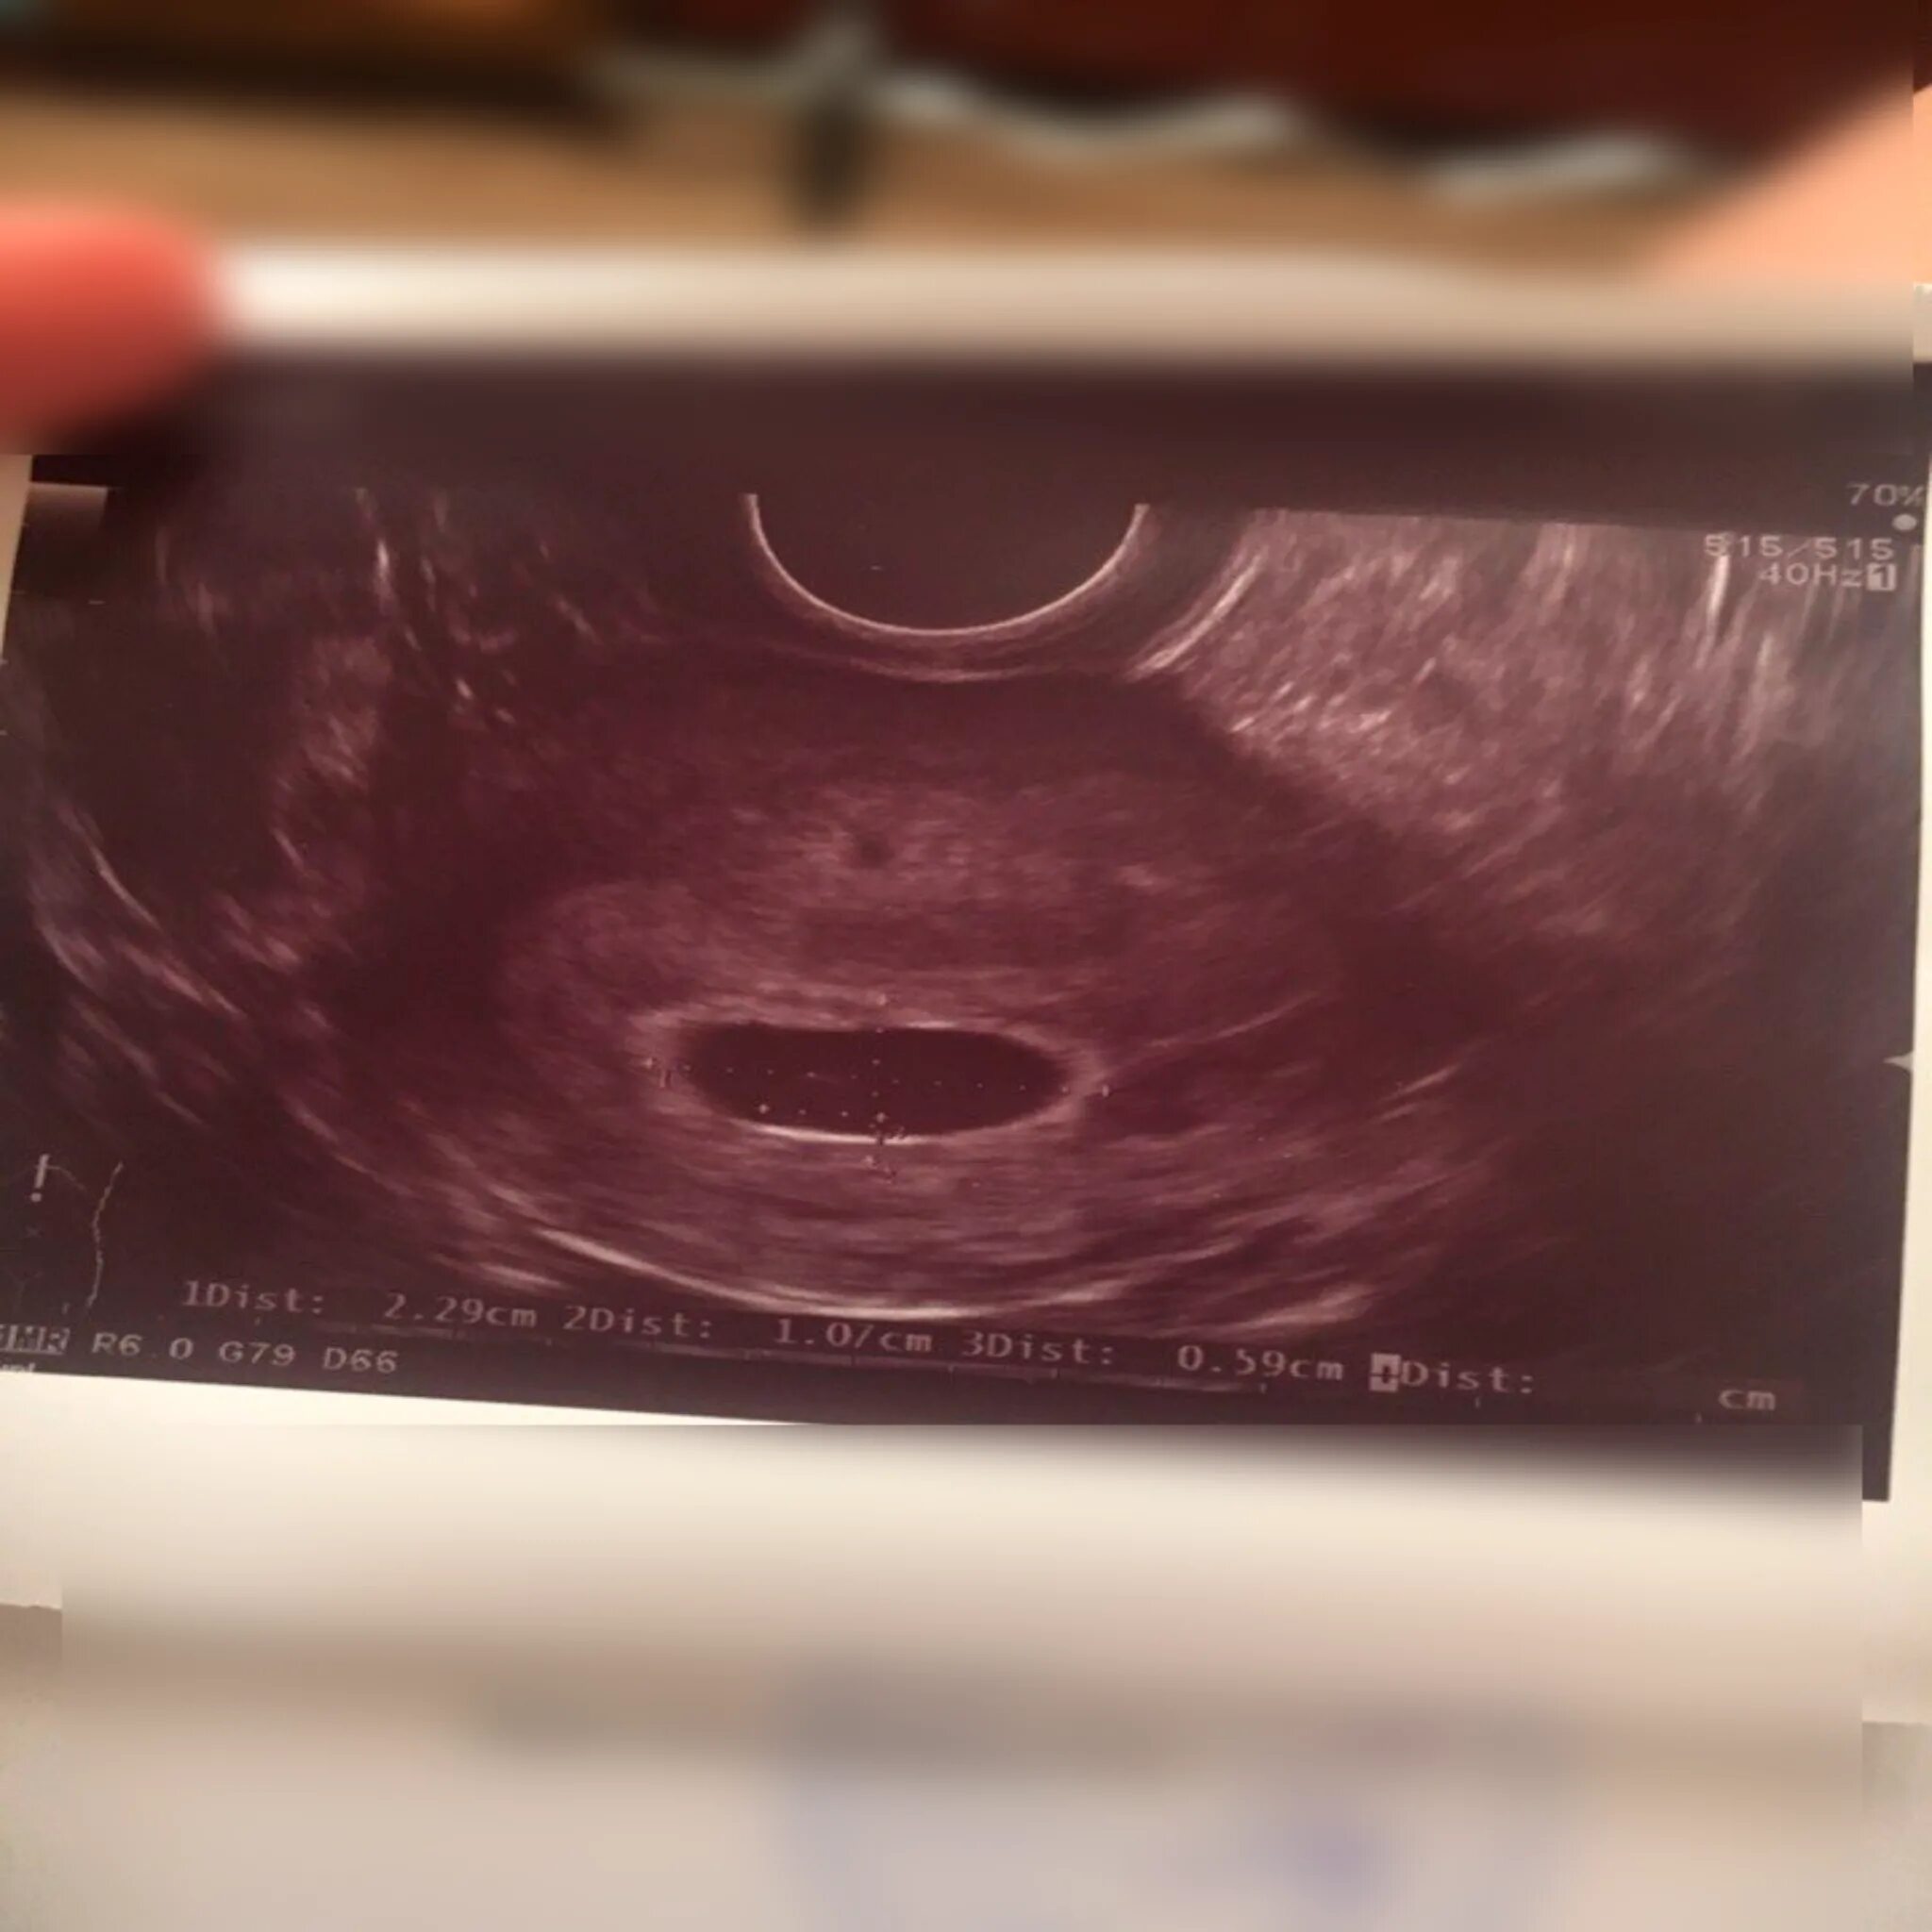

Как выглядит плодное яйцо на 5